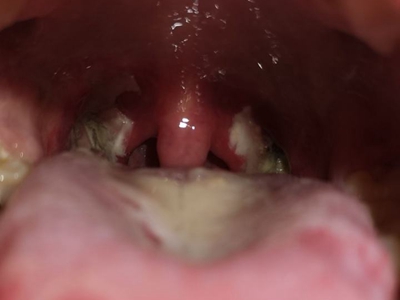

化脓性扁桃体炎扁桃体发红有白点图

化脓性扁桃体炎的病发部位存在明显的红肿表现,局部呈现鲜红色,扁桃体犹如两个肉球,其上有黄白色小点,此时患者有明显的咽痛感,并且吞咽时加重。